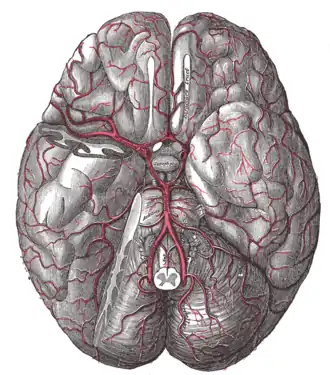

Кольцо Виллизия или Виллизиев круг

Виллизиев круг — артериальное кольцо, образованное артериями бассейна позвоночных и внутренних сонных артерий, расположенное в основании головного мозга, способствует компенсации недостаточности кровоснабжения. В норме виллизиев круг замкнут. В формировании Виллизиева круга участвуют передняя соединительная артерия, начальный сегмент передней мозговой артерии (A-1), супраклиноидная часть внутренней сонной артерии, задняя соединительная артерия, начальный сегмент задней мозговой артерии (P-1).